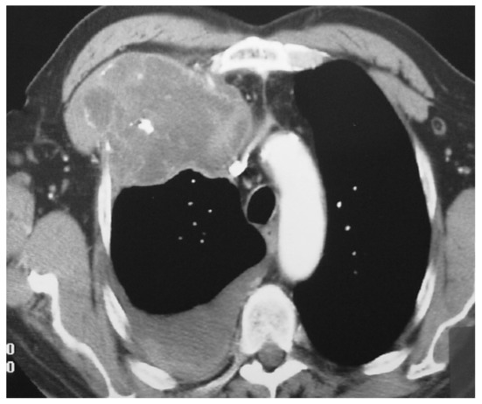

This is the most common posterior mediastinal neurogenic tumor

What is schwannoma?